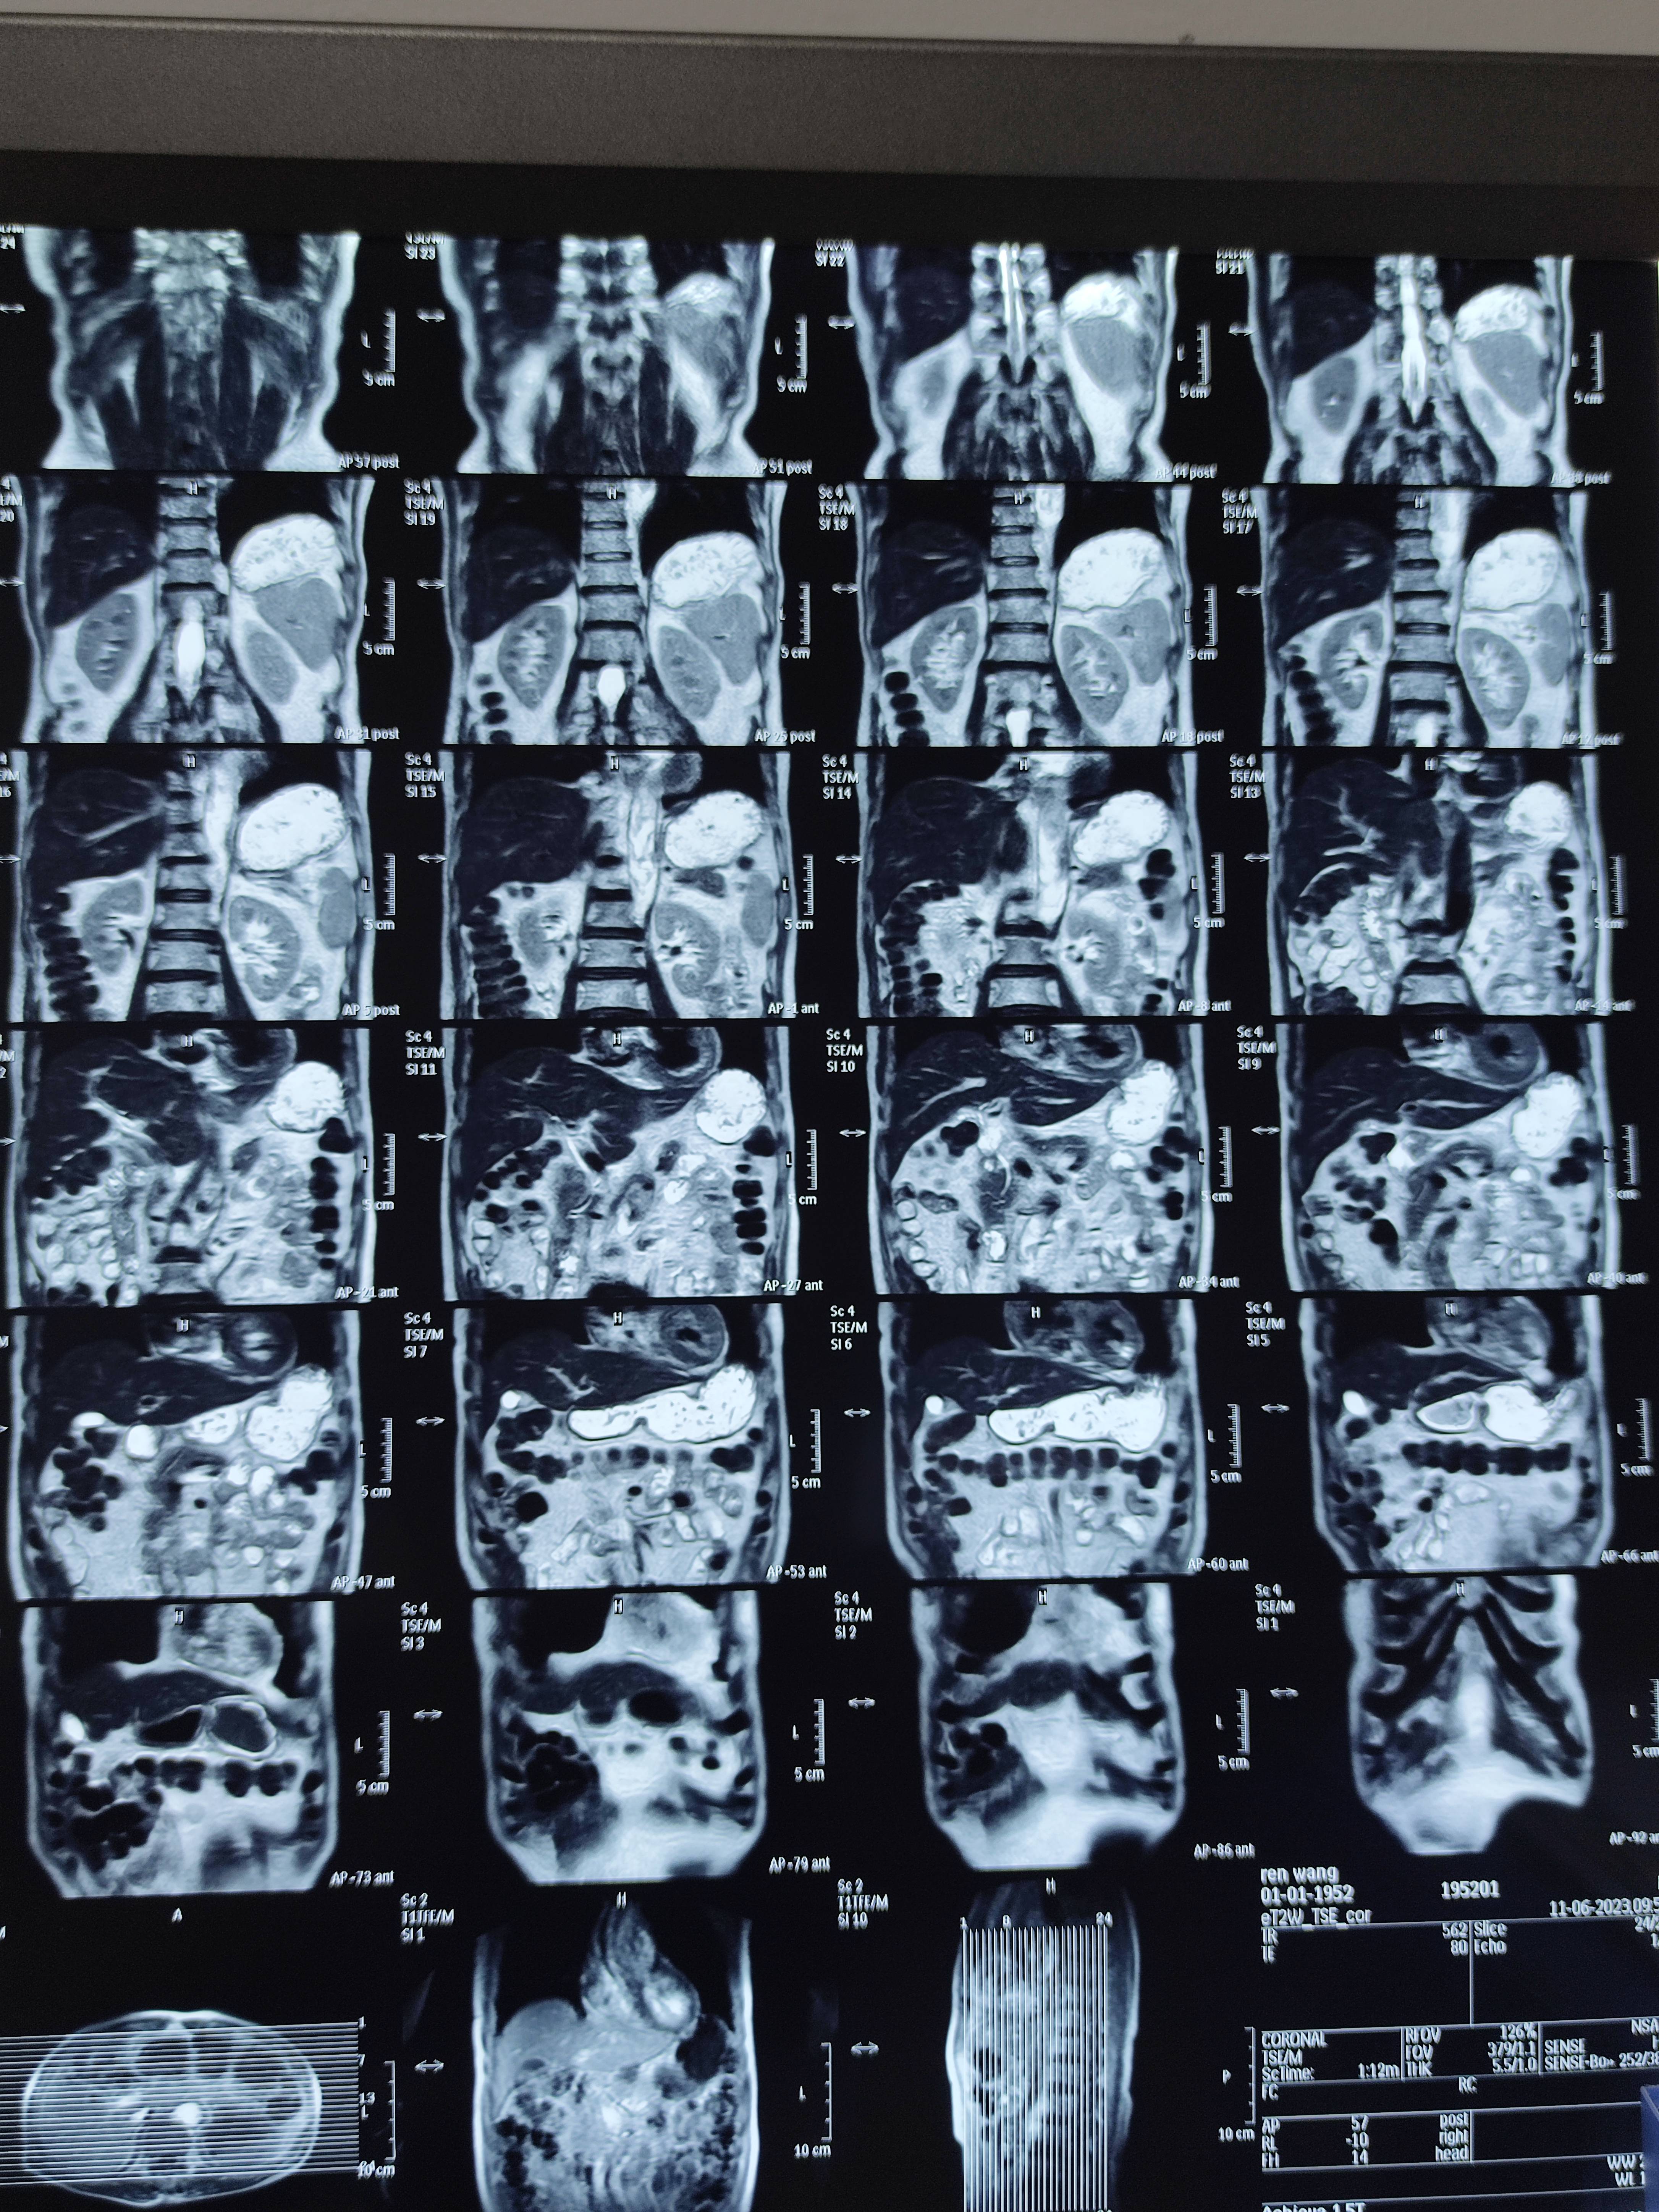

四月份癌胚抗原还是5.6,这个月到8了,持续升高。做了核磁增强,左侧桥小脑角哪有个地方不确定。肝脏核磁平扫弥散有两个点状高信号,转移也排不了,胃肠镜正常,左颈部有个变圆的淋巴结,保险点是不该加个化疗药了?咨询了陈波主任,等结果的吧!图片